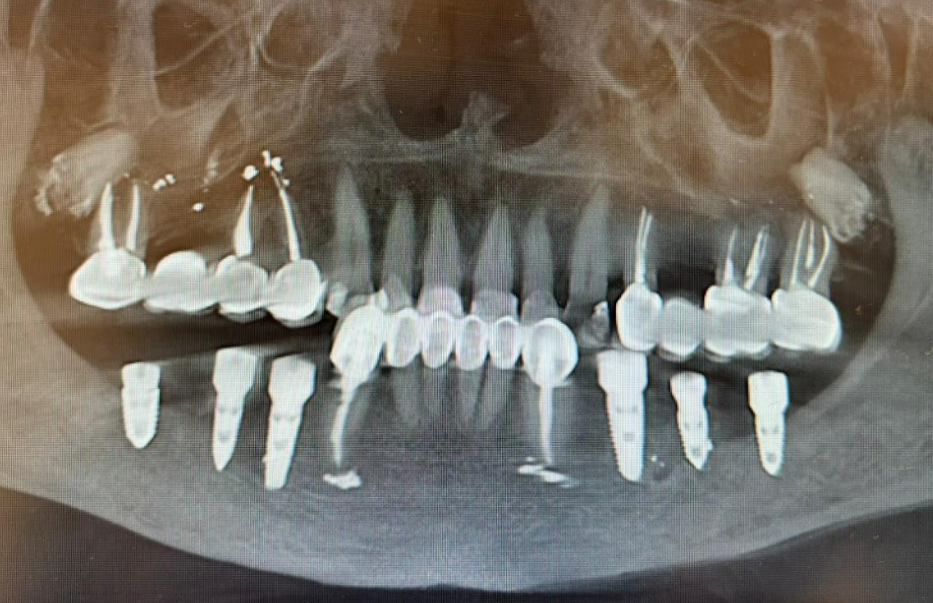

An 80-year-old female patient presented with complaints about poor quality of life due to an old clasp-retained removable denture on the mandible that required replacement. She also reported issues with the remaining compromised teeth (#34 and #48). Her general health was satisfactory, and no contraindications or limitations for implant surgery were identified. The preoperative condition is clearly visible in the provided radiographs.

During the diagnostic phase, radiographs and an intraoral scan of the patient’s mandible were obtained. Based on the digital scan data, a surgical guide was fabricated for implant placement.

In the first stage, hopeless teeth #34 and #48 were extracted. Immediate implant placement was performed: six implants were placed, three in the third quadrant and three in the fourth quadrant. A surgical guide was used to ensure precise implant positioning. The implant-abutment interface utilized a standard Internal Hex connection.